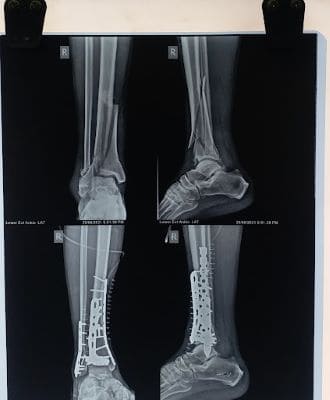

Complex Multiple Fracture Surgery

Damage usually includes injury to multiple bones, joints, ligaments, and tendons and requires intensive treatment and rehabilitation.